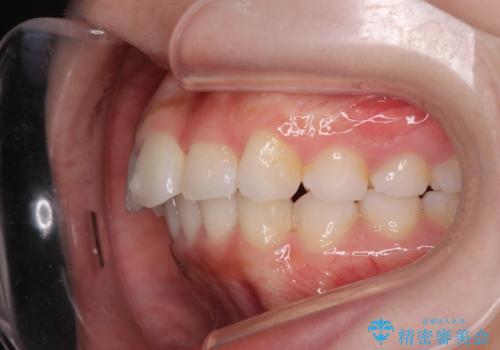

前歯のがたつき気になる。インビザラインモデレート

- 前歯のがたつきが気になるとの事で来院。

噛み合わせを確認したところ上の歯が全体的に前にある状態でした。

患者様は2のプランを選ばれたのでインビザラインモデレートで治療を行いました。

ガタつきがなくなり満足して頂けました。